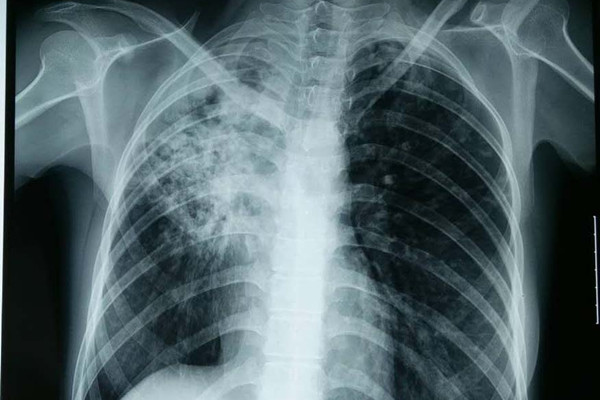

结核性胸膜炎可见于初发结核病,也可见于复发的结核病。约百分之二十五的成人结核病患者以肺外结核病为首发表现,结核性胸膜炎是肺外结核最常见的形式之一。与肺结核不一样,结核性胸膜炎通常呈急性起病,约百分之三十的患者在1周内出现症状,百分之七十的患者在1个月内出现症状。